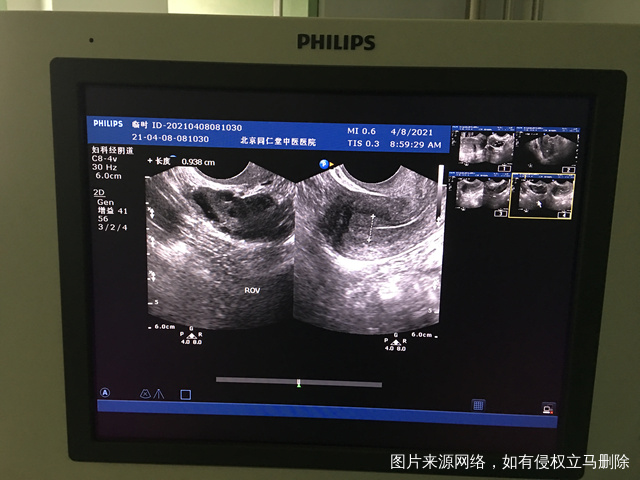

您好我月经不规律上次月经3月2日请问我现在这